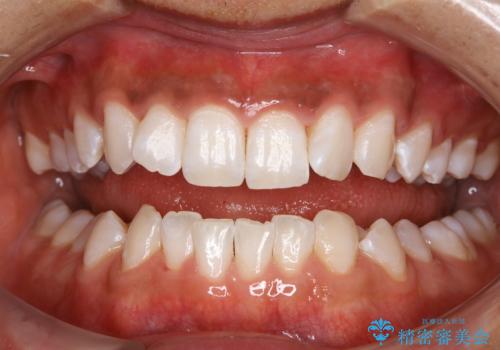

処置後は艶のある綺麗な白さになりました。

ご希望の自然な白さに、トーンアップしたとのことで満足していただけました。